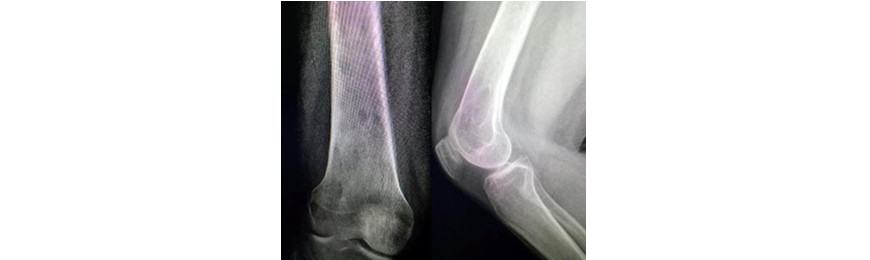

Volver a los detalles del artículo Sarcoma sinovial con invasión medular